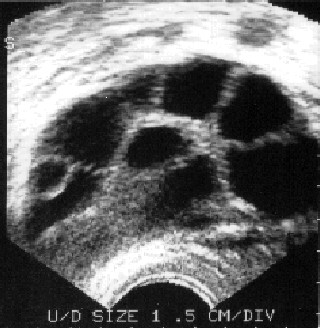

И так,в пятницу,17 мая мое узи покажет вот такую картину

поэтому в понедельник,20 мая,как и планировали у меня будет моя счастливая и урожайная пункция! фолики будут дозревшие и с яйцеклеточками)УРА!УРА!УРА!

вот они какие красивенькие эти мои желточки)